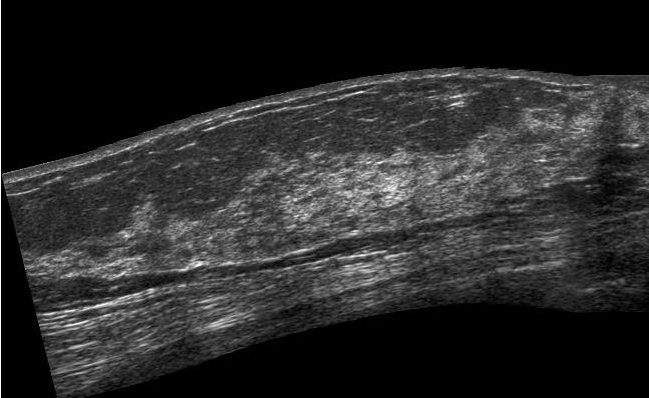

Breast Sonography (Sonomammography)

Breast ultrasound is used to help diagnose breast abnormalities detected during a physical examination (such as a lump or nipple discharge) and to characterize further findings or abnormalities seen on Xray mammography.